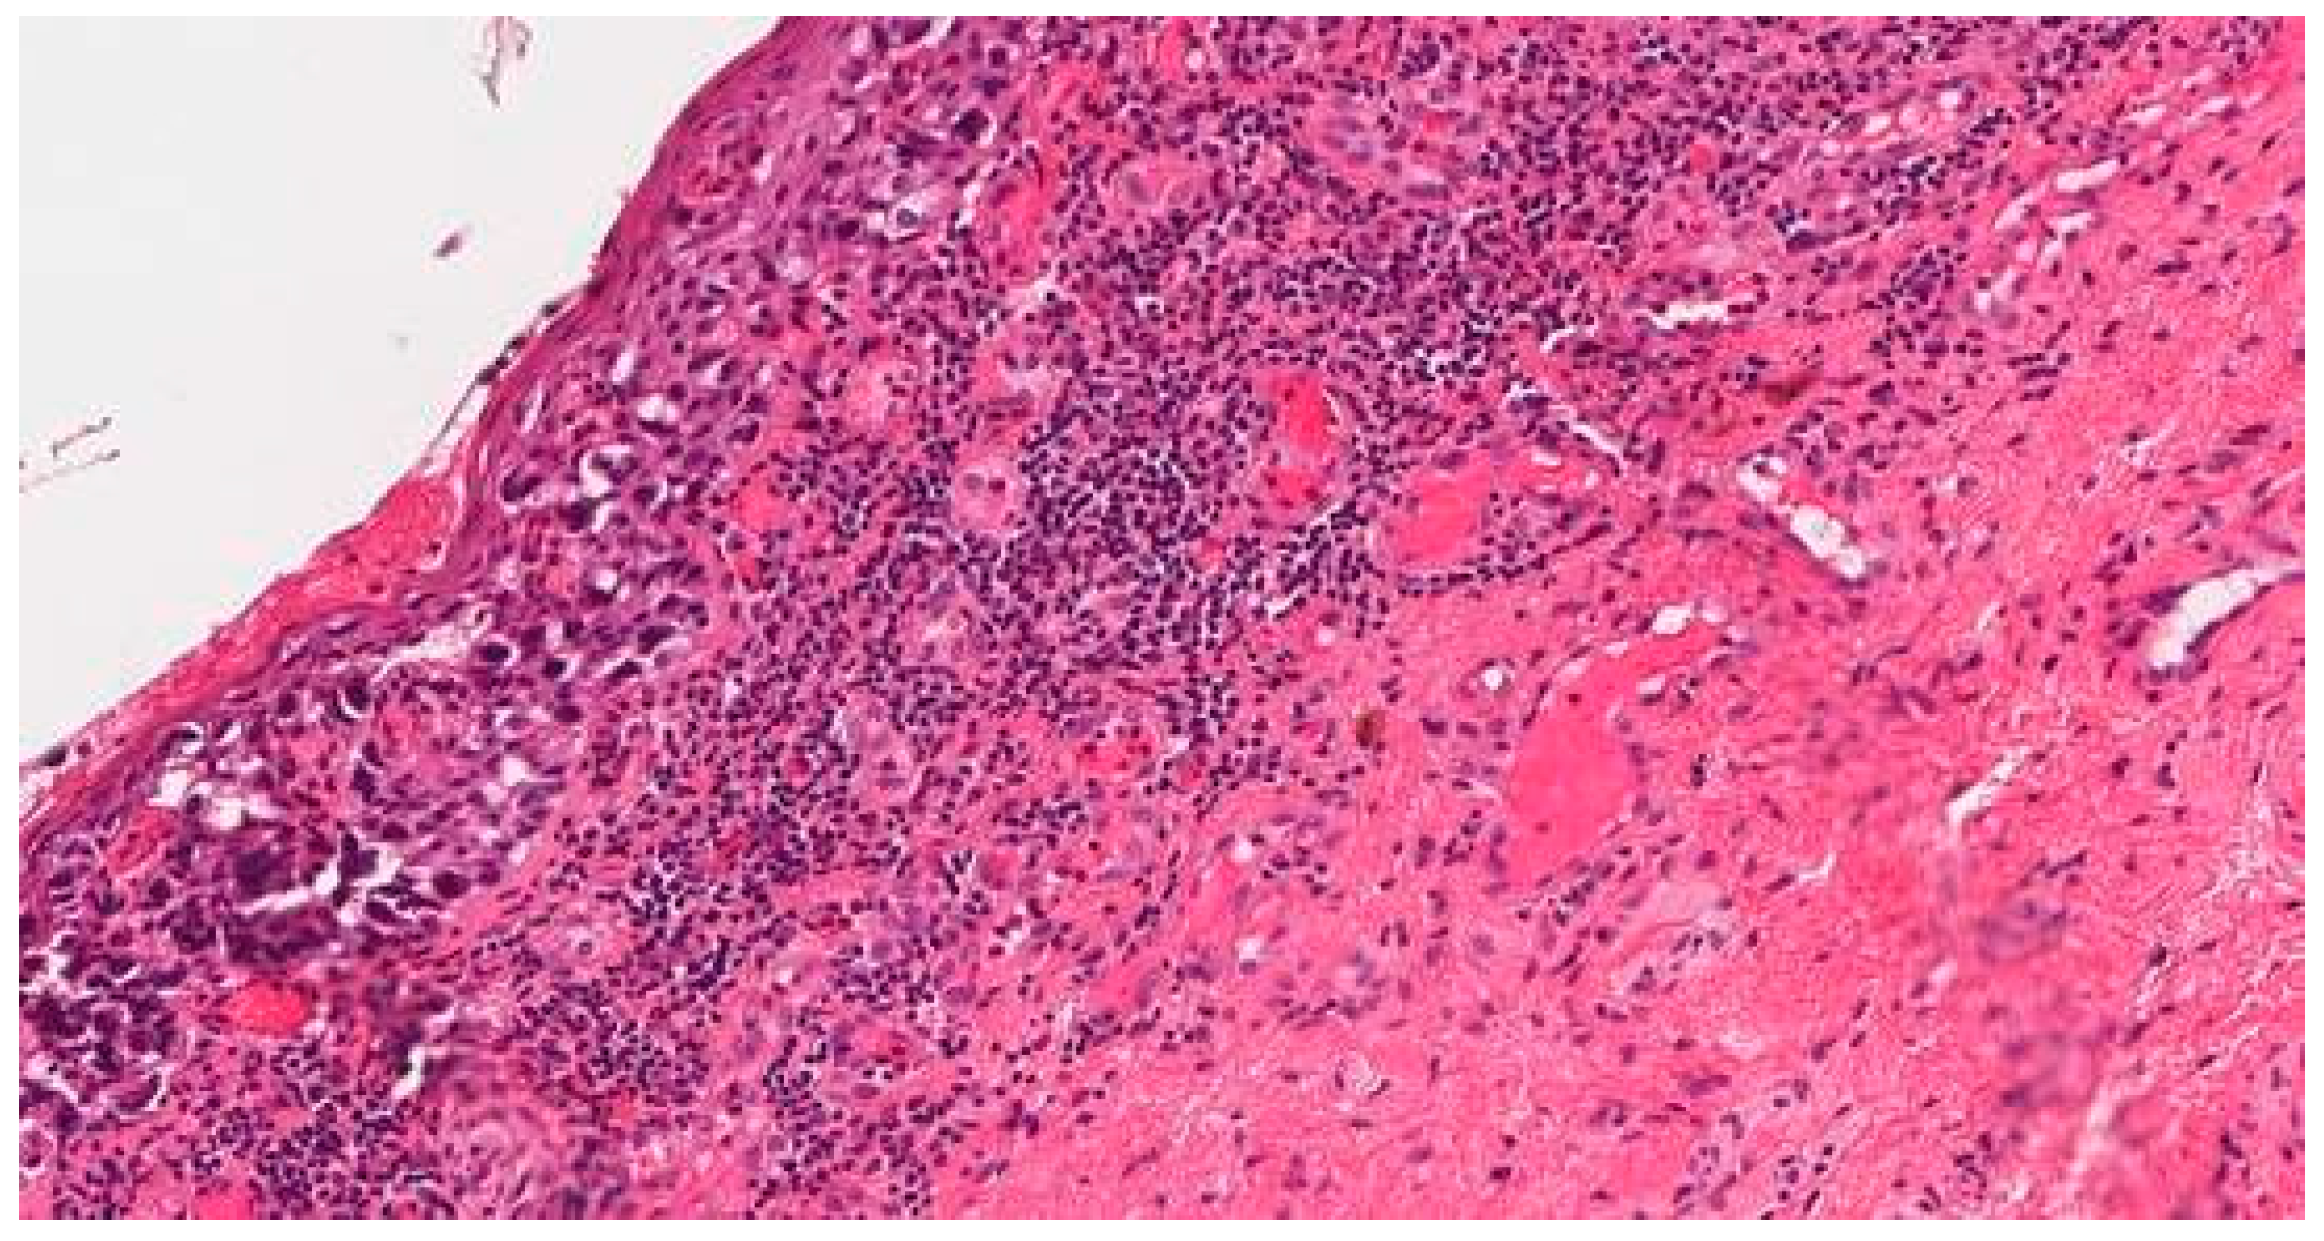

Multiple Rare Primary Malignancies: A Mixed Squamous Neuroendocrine Adenocarcinoma of the Cervix, Metastasized Carcinosarcoma and Extramammary Vulvar Paget’s Disease Case Report

2. Case Report